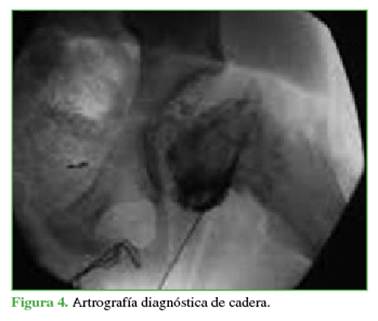

Se realizó una punción-aspiración con el paciente bajo anestesia para evaluar el grado de desplazamiento epifisario1 y evacuar el hematoma articular.2 Luego, con poco líquido de contraste, se efectúo una artrografía que constató el desplazamiento y su inestabilidad. La resonancia magnética es otro estudio para llegar al diagnóstico, si se duda de la inestabilidad, pero se debería contar con un resonador cerca o dentro del quirófano para realizarla en el mismo acto anestésico (Figuras 4 y 5).